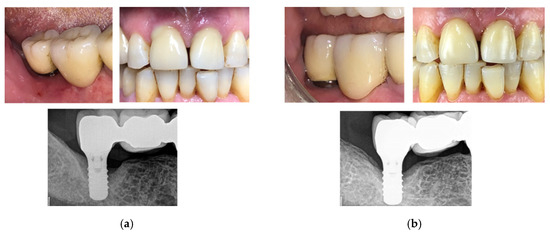

The third clinical case is a 75-year-old man with swelling, bleeding on probing, and exudate presence. Following a session of oral hygiene, the patient was treated with the new developed device. After four therapeutic sessions (two per week, with increasing intensities—up to 70%, 80%, 90%, and 90% of the maximum power in the first, second, third, and fourth sessions, respectively; four consecutive signal deliveries were used in the first three sessions, with seven in the last one), swelling was reduced and bleeding on probing was resolved. Continuing the treatment with monthly cycles, the implants were recovered after approximately eight months (Figure 15). Periodical check-ups were planned.

The fourth clinical case is a 75-year-old woman with bleeding and exudate presence. After two therapeutic sessions (one week, at 90% of the maximum power), tissues conditions definitely improved and the exudate presence was clearly reduced after two weeks (Figure 16).

In all the cases, the patient-reported outcomes were evaluated, underling that the first effect of the treatment was recognized in the immediate disappearance of pain and symptoms perceived by the patient.

Figure 15. Clinical case No. 3: dental implant (a) before and (b) after the treatment.

Bioengineering 07 00087 g015

Figure 16. Clinical case No. 4: dental implant (a) before and (b) after the treatment.

Bioengineering 07 00087 g016